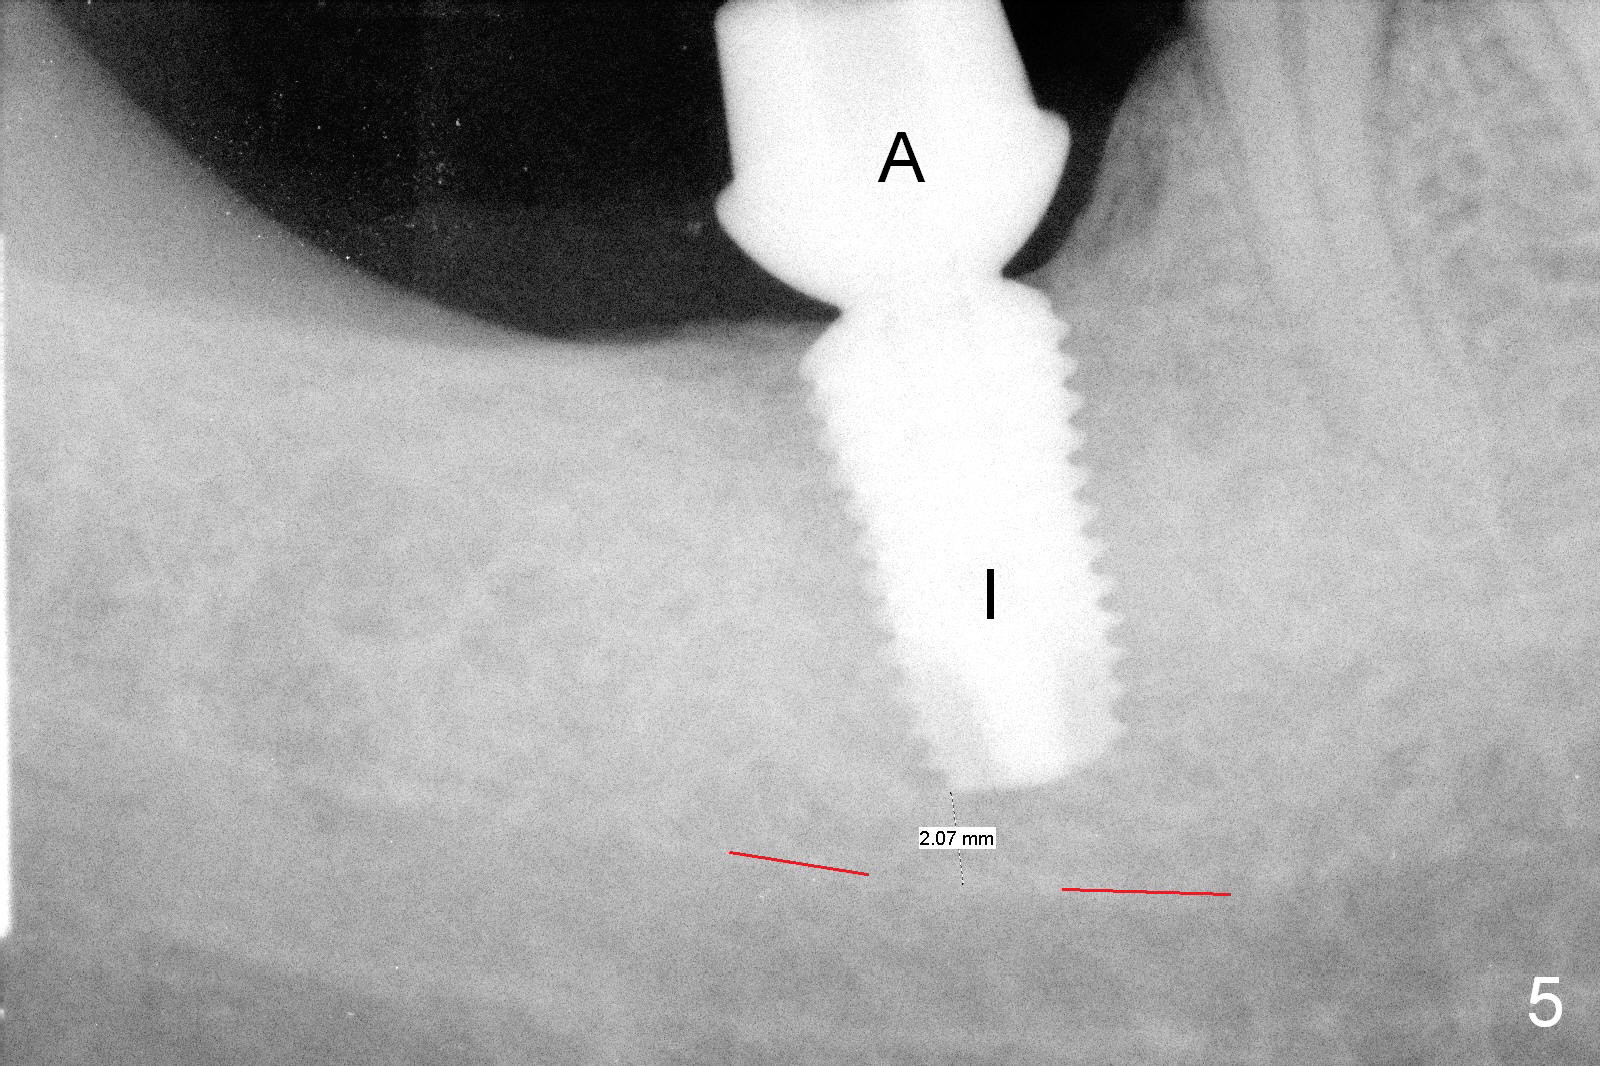

The 61-year-old man is nervous about dentistry. When he returns for #4 implant, he wants an implant at #31 first. Fig.1 shows #31 crown fracture after root canal therapy. Three years after crown placement, there is sign of mesial root fracture (Fig.2 arrowheads). Four years post extraction, bone height is 12 mm (Fig.3 parallel pin 10 mm). An extra wide implant is to be placed, since there is enough bone width. With infiltration anesthesia, the patient feels pain when a 5.4x10 mm drill is being used, 1 mm short of the desirable depth (Fig.4). After Inferior Alveolar Nerve block, the last drill reaches the depth. A 5.9x10 mm implant is placed with insertion torque 50 Ncm (Fig.5 I). A 7.8x4(3) mm cemented abutment (A) is placed immediately. After suturing, the restorative portion of the abutment is covered by the gingiva. It is probably due to over tightening the sutures. It would be ideal to adjust the gingival level before tightening the second suture.